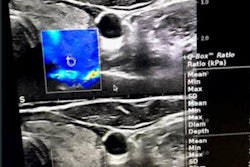

Meanwhile, researchers have found that an AI algorithm could offer significant value in breast ultrasound. A team from China reported that their model, which analyzes both grayscale and contrast-enhanced ultrasound, (CEUS) could perform comparably to ultrasound experts.